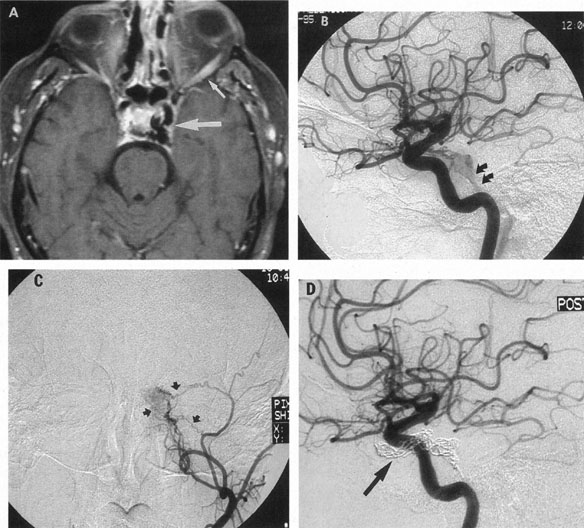

In some persons, the cavernous sinuses have existing or potential connections to the deep venous system of the brain. Indeed, this may be the preferential route of venous drainage from all or part of the cavernous basal sinus complex. Therefore, the clinical appearance of orbital venous hypertension associated with a cavernous dAVM may be relatively minimal, but arterialized flow is transmitted instead chiefly via venous dural channels draining the medial aspects of the temporal lobes and the basal vein of Rosenthal. The latter drains an extensive deep parenchymal territory, including part of the posterior fossa. This effluent pattern explains how some cavernous dAVMs or CCFs present with relatively minor outward physical signs but with serious complications from cortical venous hypertension (Fig. 18), elevated intracranial pressure (a form of secondary pseudotumor cerebri syndrome; see Chapter 5, Part II), temporal lobe seizures, brain parenchymal hemorrhage caused by venous infarction or venous rupture (Fig. 19), or edema of the posterior fossa structures.119

Fig. 18. A 25-year-old man developed severe right-sided proptosis and a loud bruit at the time of a vehicular accident. Lateral projection of the right internal carotid artery in the early arterial phase (A) and late arterial phase (B) in anteroposterior projection demonstrate immediate opacification of the superior and inferior ophthalmic veins (straight arrows), the inferior petrosal sinuses (curved arrows) and of the deep parenchymal veins of the right hemisphere (open curved arrows). The fistula was related to a large carotid laceration involving the cavernous and supraclinoid segments of the right internal carotid artery. The artery could not be preserved at the time of treatment. C: Latex balloons (open-ended arrowheads) were placed in the fistula and within the carotid artery at the time of treatment. (Courtesy of Frank Huang-Hellinger)

Fig. 19. A 30-year-old woman presented with headaches. Lateral views of left (A) and right (B) internal carotid arteriograms demonstrate developmental venous malformation of the cribriform plate supplied by both ophthalmic arteries. Note subarachnoid veins of the anterior cranial fossa (curved arrows). In addition, the right ophthalmic artery (B) has a cavernous origin (arrow), a vestige of the dorsal ophthalmic artery that usually atrophies in fetal development.